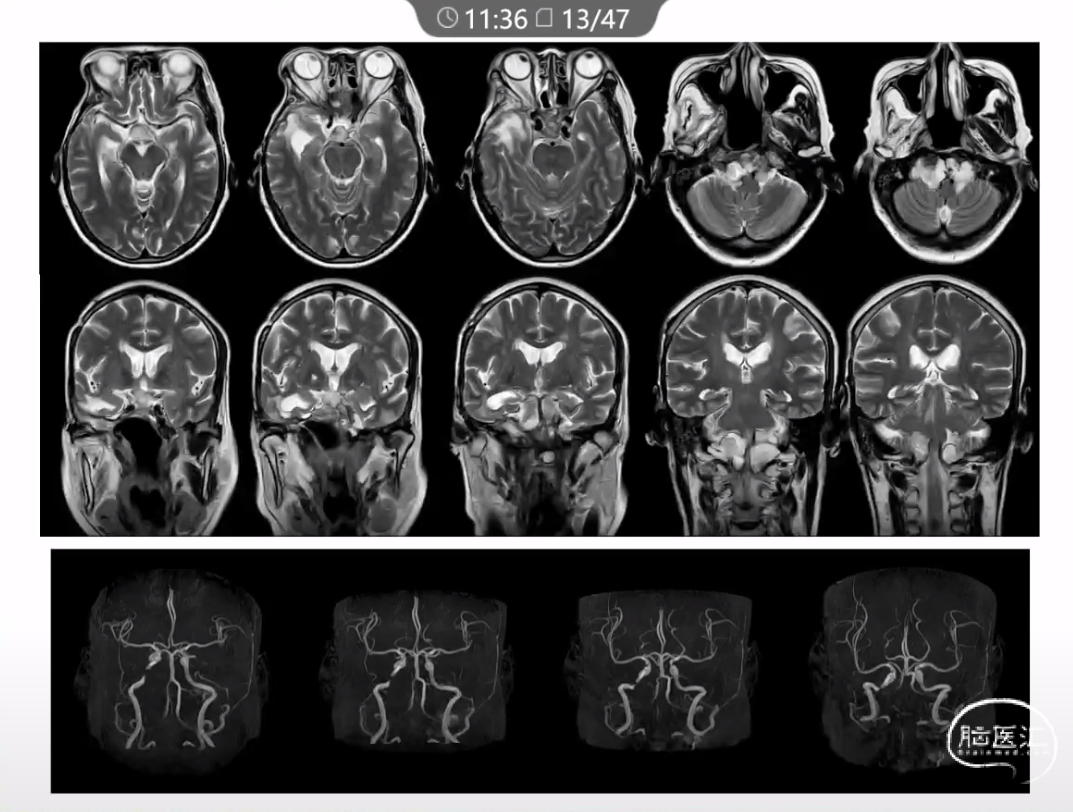

本文主要内容为:脊索瘤临床特点、治疗选择,以及多个手术病例。